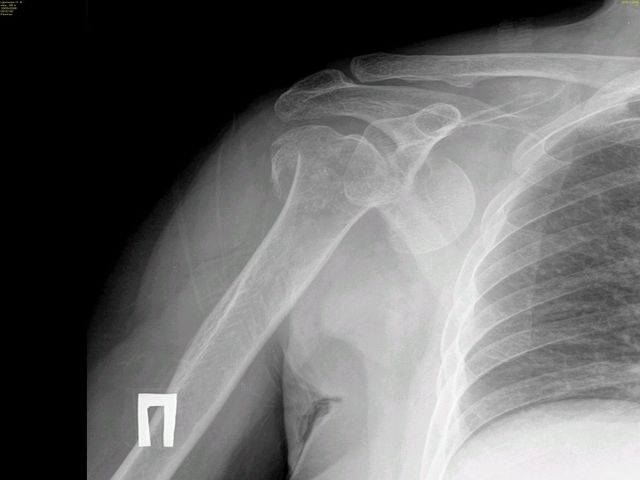

Re: несвежий переломо-вывих плеча

Надо бы увидеть снимки. А лучше бы и КТ с трехмеркой.

Не передаются фото, хотя все условия выполняются. Попробую еще раз. Простите.